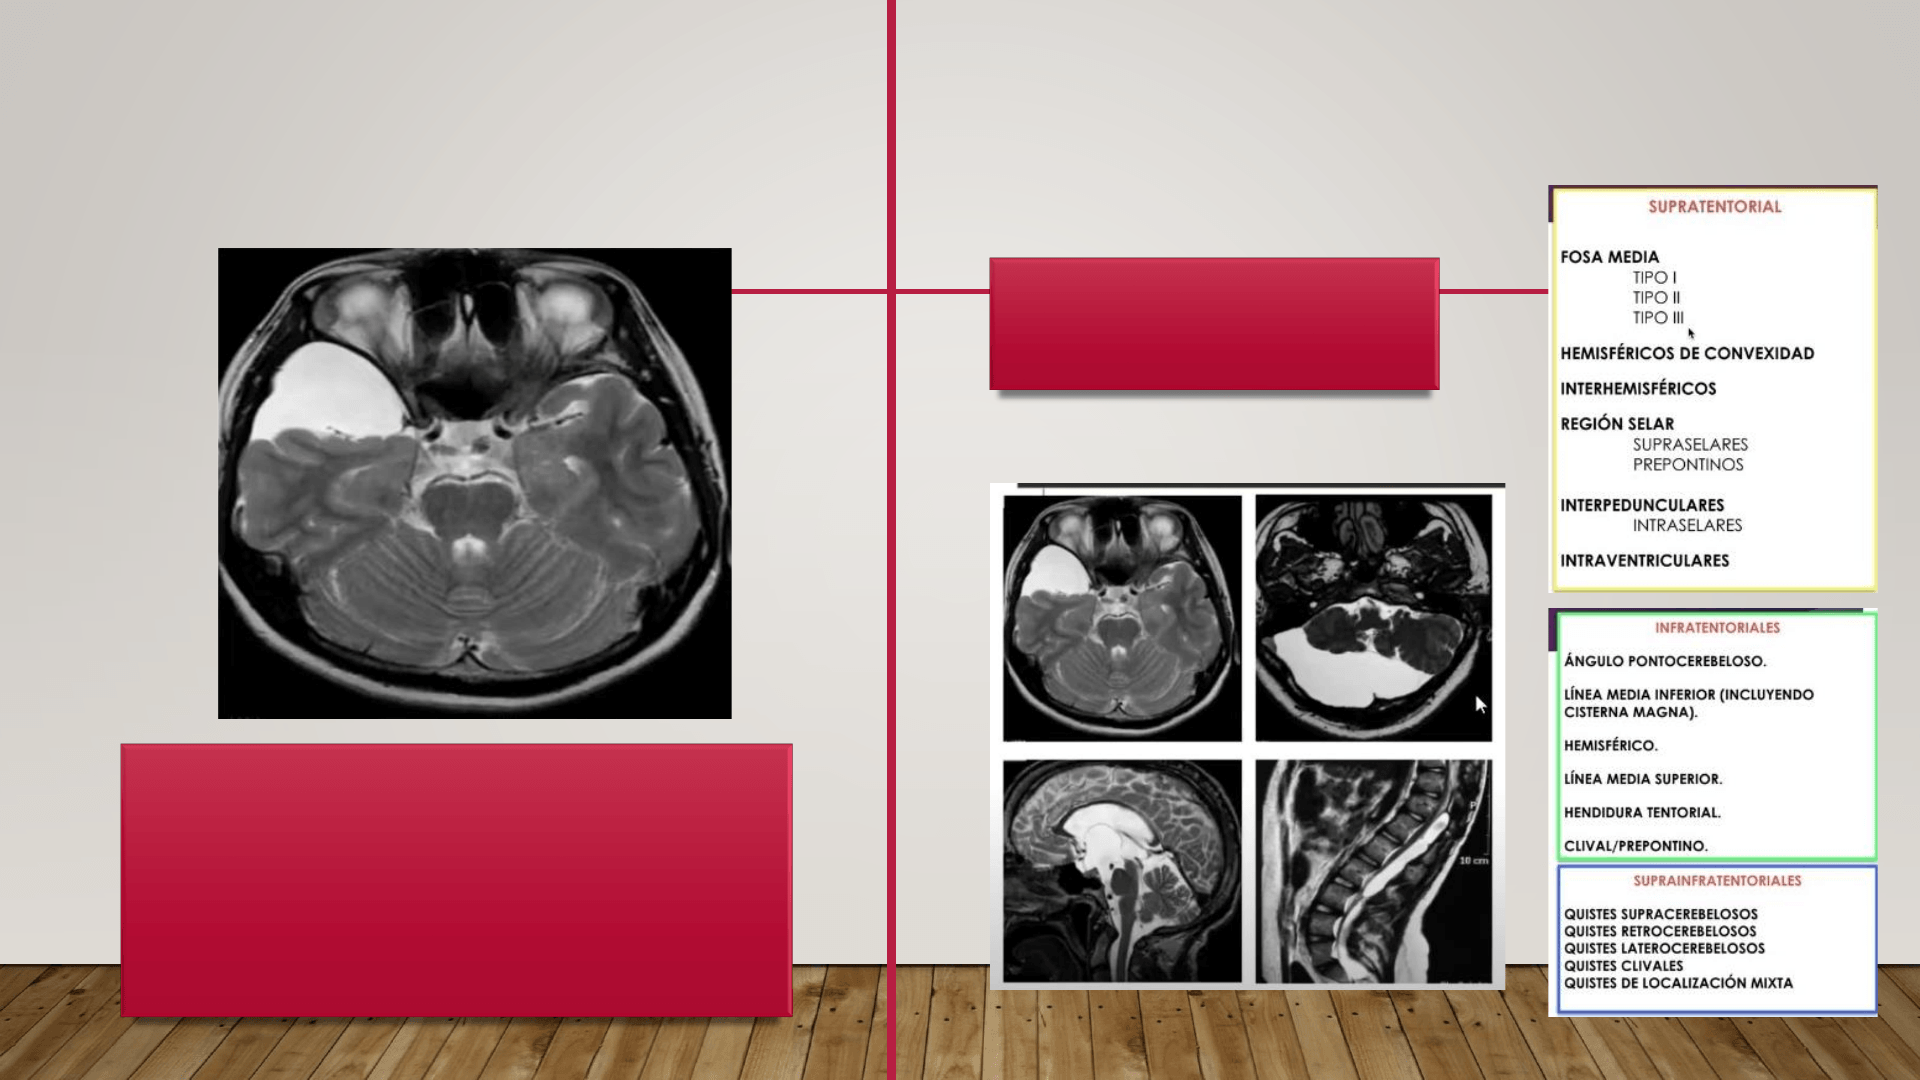

La porencefalia se define como un defecto de cierre neural que

se caracteriza por espacios quísticos en el parénquima cerebral

y en el subaracnoideo.

El término, quiste porencefálico se utiliza para definir una

cavidad en el parénquima cerebral y que pueden comunicar o

no con los ventrículos, llenos de LCR, en el parénquima.

Las cavidades a menudo se comunican con un ventrículo, pero también

pueden ser quistes cerrados (es decir, no comunicantes) llenos de líquido.

Puede haber un aumento de la presión intracraneal e hidrocefalia

progresiva en la porencefalia, especialmente en las formas no comunicantes,

aunque es raro.